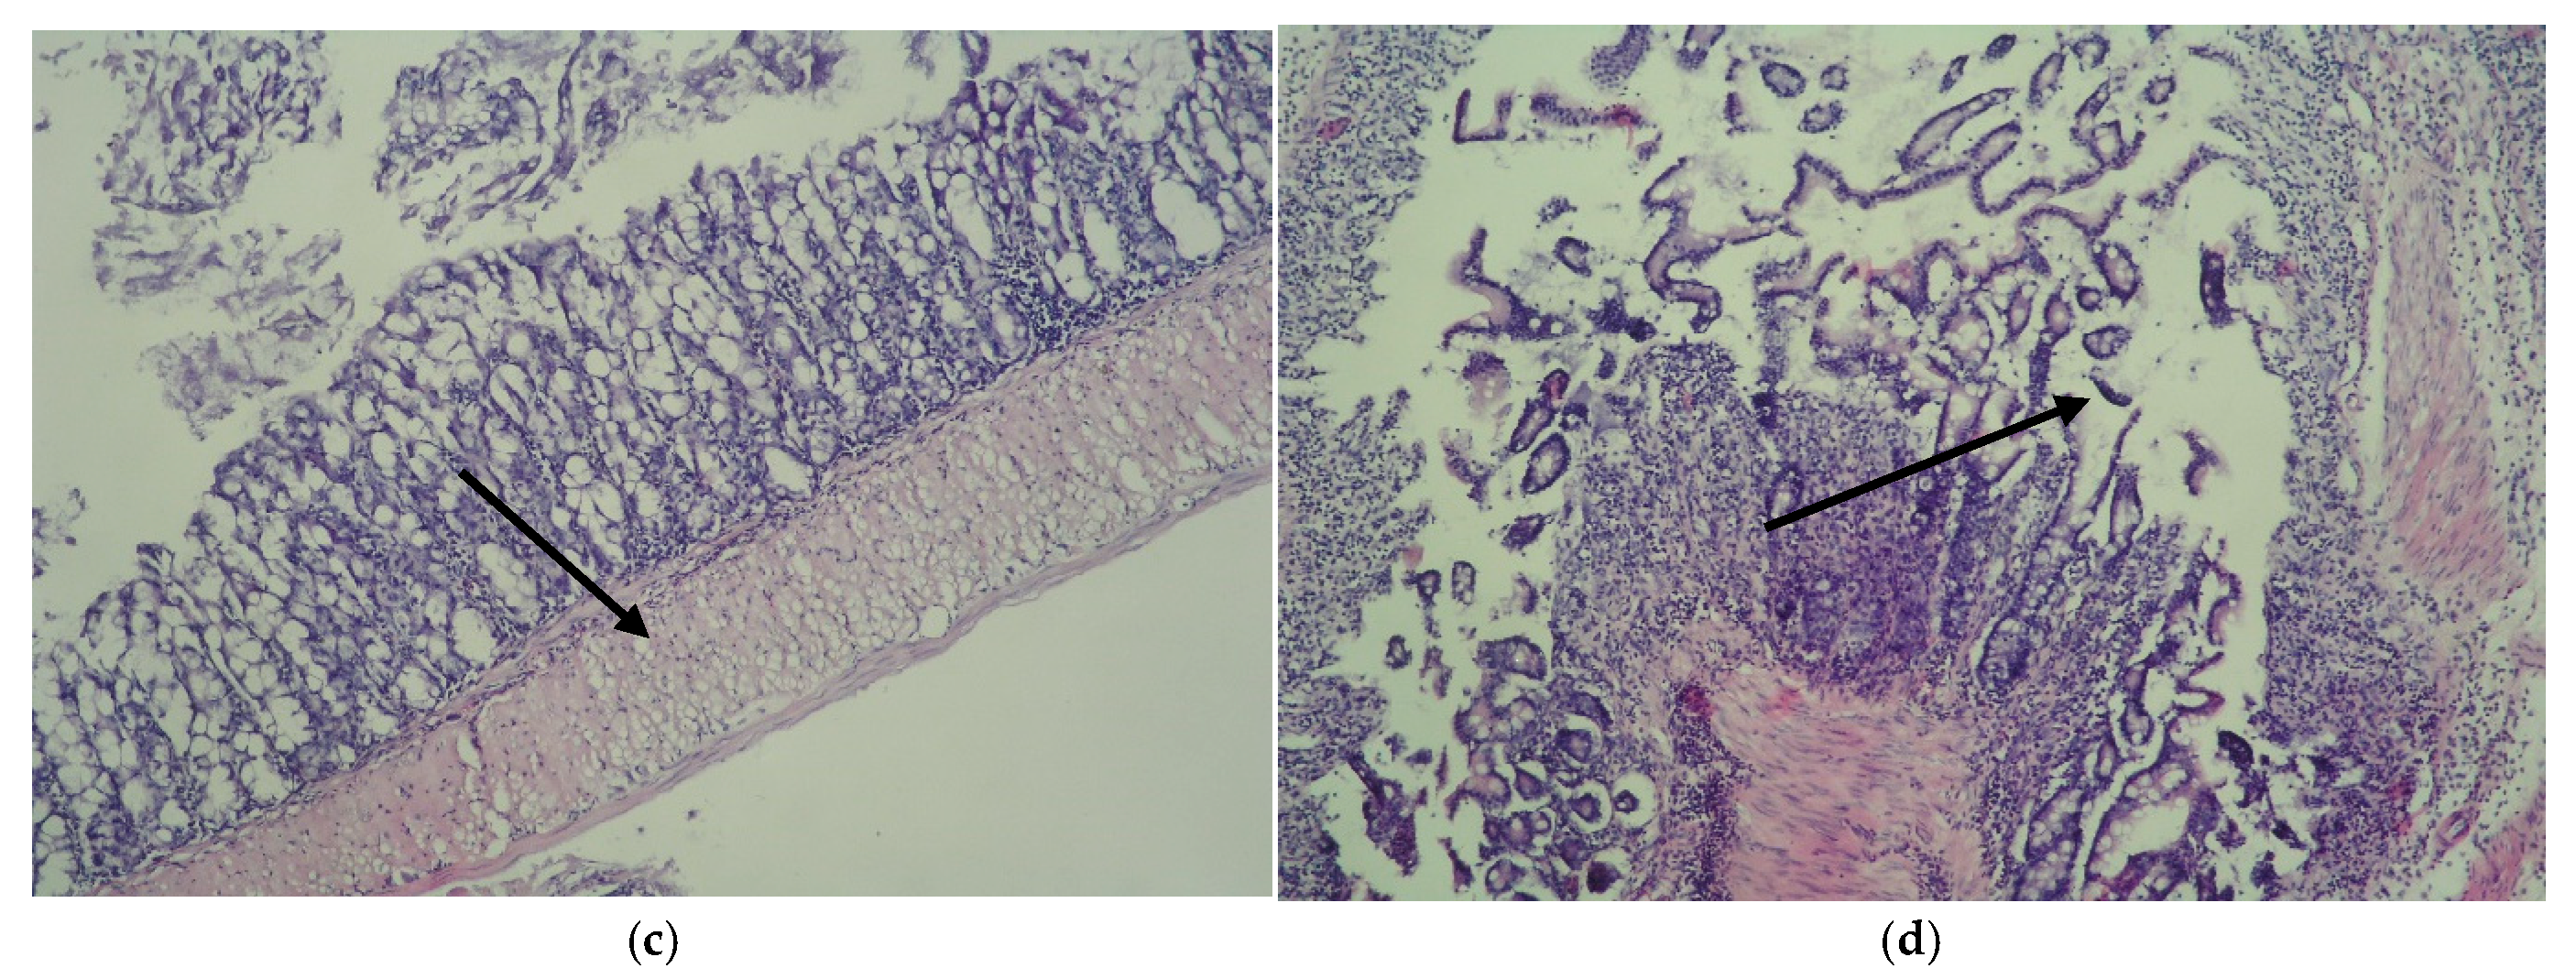

Histopathological Findings